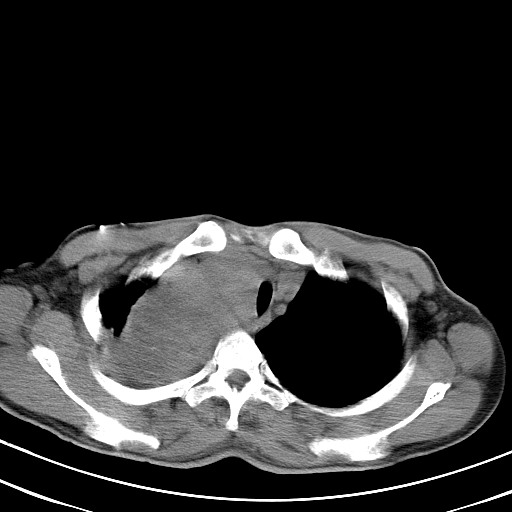

以下是引用汪涛同志在2007-8-2 0:40:00的发言:[br]病变虽然广泛,同时侵及双侧纵隔,但是无论左侧和右侧上下观察都是与右侧颈部甲状腺相延续的,而且强化幅度基本一致,又同时具有恶性病变病变的某些特征:肿块过大且密度不均,部分层面与正常纵隔结构分界不清,结合病史已有两年,考虑:胸内甲状腺肿恶变可能。[br]